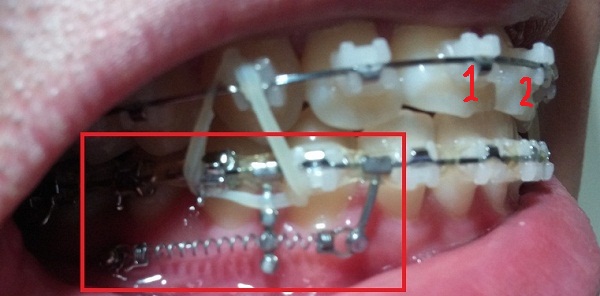

[스프링 옆면]

+스프링사이에 또 다른 쇠기둥 보이시죠?! 저건 스프링이 잇몸에 닿아서 짓눌리지 않게 하기 위해서 해둔 조치랍니다.(제가 눌려서 아프다고 호소했더니 저런 방법으로 해주셨어용^^)

[스프링아래서 본]

-하악 파워체인 엇갈려서 걸어놓기(후기 23화와 같은 치료),

-하악 스프링 + 덧대기(잇몸이 눌리지 않게)